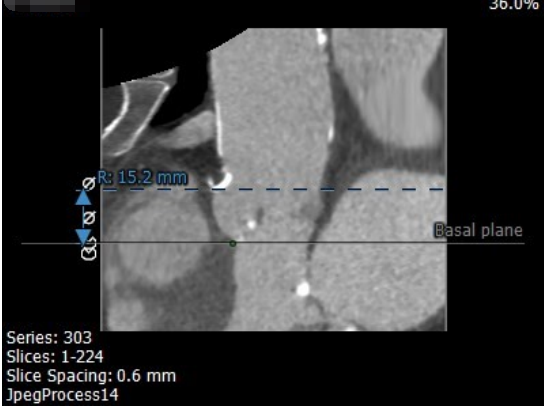

考虑到患者年龄较大,并发症多且复杂,心功能差,身形瘦小,无法耐受常规的开胸手术,经过术前综合评估,我们建议患者实施经导管主动脉瓣置换术(TAVR),通过介入的方式,将组装好的主动脉瓣经导管置入体内,完成主动脉瓣的置换。

经过内外科团队讨论,由于右桡动脉已经闭塞,在不影响后续经股动脉实施TAVR手术的前提下,治疗团队决定先由心内科经左桡动脉途径,处理冠状动脉主干和左前降支钙化性病变,同时处理左锁骨下动脉钙化性病变。十几个小时后再由心外科行TAVR手术。